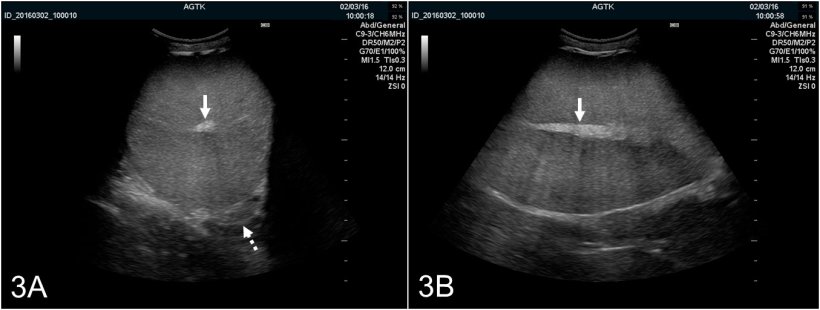

I testicoli possono esser ecografati longitudinalmente o transversalmente (figura 2A e B). Per determinare la circonferenza del testicolo, si devono usare immagini trasversali. Il tessuto testicolare sano ha una ecogenicità media e presenta una ecotessitura omogenea, con la rete testis iperecogenico nel centro del testicolo (figura 3A e B).